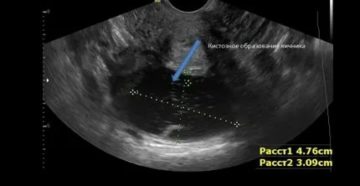

Киста яичника на УЗИ Яичники — это парные органы, имеющие огромное значение при зачатии. Именно…